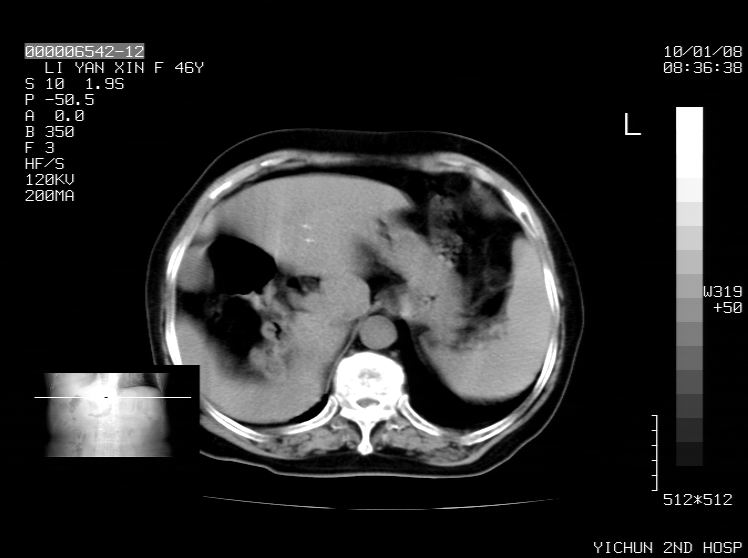

右侧膈膨升,胆囊壁厚,右侧肾脏缺如。病史?

右侧膈膨升,右肾脏切除术后

右侧膈膨升,肝内钙化灶,胆囊壁厚,右侧肾脏缺如。病史?

右膈膨出,肝脏变异,肝内钙化,右肾缺如,脾大。

右侧膈膨升,肝内胆管结石?

右侧肾脏缺如。病史?

右侧膈膨升,胆囊壁厚,右侧肾脏缺如,增强,腔静脉旁是否是移位肾

肝脏变异致膈升高,肝左叶肝内胆管结石.右肾萎缩,左肾代偿肥大.

胆囊ct未见确切异常,请结合b超。右侧肾窝未见确切肾脏影,右肾萎缩?异位?

右侧膈膨升,肝内钙化灶,胆囊壁厚,右肾萎缩或发育不良。